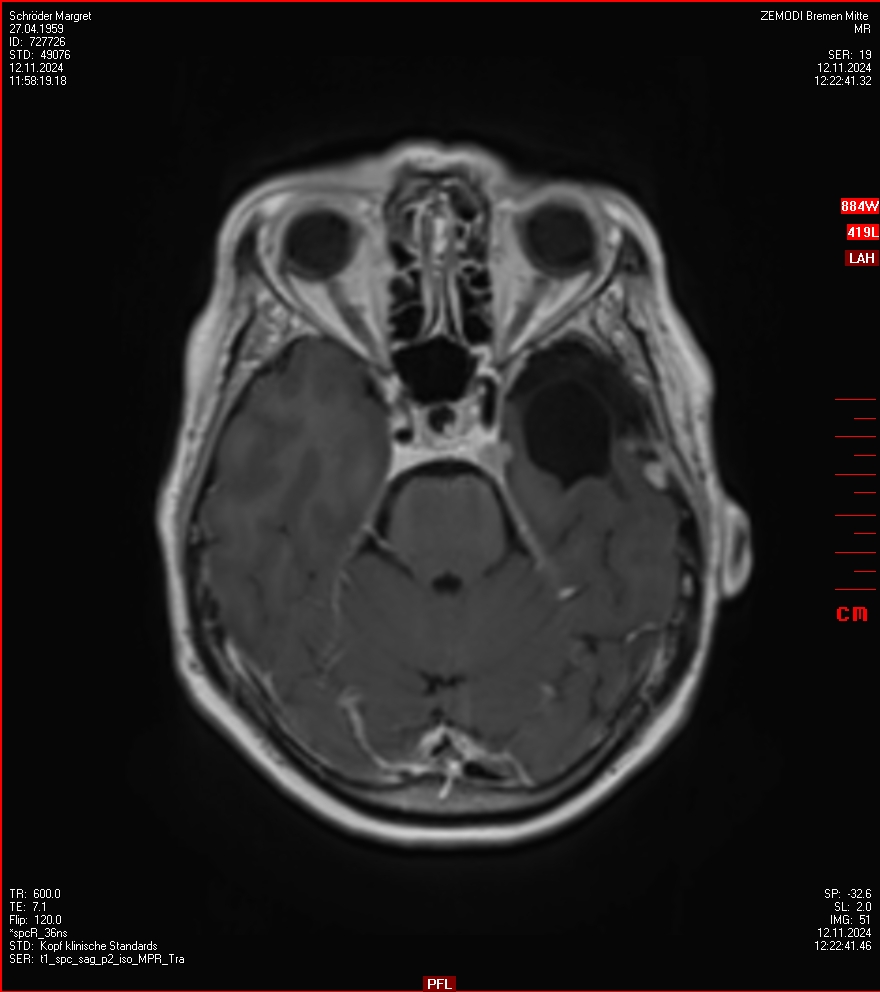

MRT vom 12. November 2024

So nun ein paar neue Bilder aus meinem Kopf. (Durch klicken bekommt man eine größe Ansicht eines Einzelbildes).

Die letzten drei Bilder Zeigen aus meiner Sicht den Tumor, der im Jahr 2021 bestrahlt wurde.

Ich denke, in den letzen 12 Monaten sind da ein paar Rezidive gewachsen,  vor 12 Monaten waren sie auch schon zu erkennen - vorher noch nicht. Nun hoffe ich auf den Rat des Spezialisten. Hoffendlich kann man etwas machen.